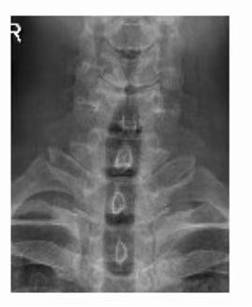

术前 图片1

术前 图片2

术前 图片3